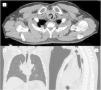

Los tumores glómicos de tráquea son lesiones de presentación inusual o rara, representan el 2% de los tumores de tejidos blandos, son benignos, y se generan en el tejido mesenquimal de las anastomosis arteriovenosas1. La presentación clínica es inespecífica y con frecuencia se diagnostican erróneamente con enfermedades respiratorias como asma bronquial, bronquitis, entre otras. Las manifestaciones clínicas severas se dan cuando se obstruye>70% de la luz traqueal y se dan con la presencia de disnea de mínimos esfuerzos2. Su diagnóstico puede ser incidental en estudio de imágenes, o con la presentación de síntomas respiratorios de larga evolución u obstrucción severa de la vía respiratoria superior. Continúa el debate respecto a su tratamiento y los resultados a largo plazo, teniendo en cuenta las diversas alternativas a la resección traqueal segmentaria, incluido el tratamiento endoscópico o la radioterapia. El tratamiento quirúrgico tiene como objetivo eliminar la obstrucción de la vía respiratoria, curación definitiva en lesiones de crecimiento lento y prolongar la supervivencia a largo plazo3. Informamos de un caso de tumor glómico de tráquea con obstrucción de la luz traqueal del 90%, que requirió plastia traqueal con la resección tumoral como tratamiento definitivo, describimos el manejo y actualización de la literatura. Hombre de 55 años con antecedentes de cirugías previas de herniorrafia umbilical, hemorroidectomía, septoplastia, covid 19 (enfermedad leve), quien presentó desde hacía 6 meses tos seca, ronquidos, acompañado de disnea de medianos esfuerzos, recibiendo tratamiento médico para asma bronquial sin disminución o remisión de los síntomas. En la tomografía de cuello y tórax se observó tumor de densidad definida ligeramente irregular, protruyendo desde la pared posterior y lateral derecha aproximadamente a 3,5cm subglótica, pediculada de 12 x 15mm de diámetro que se proyecta hacia la luz traqueal que mide 12,5 x 22 x 15mm, densidad ligeramente heterogénea con coeficiente de atenuación entre – 26 y 17 UH que condiciona estenosis de luz traqueal del 90%, sin compromiso esofágico y sin evidencia de adenopatías locorregionales (figs. 1 y 2). En la broncoscopia se evidenció una masa vegetante infiltrativa que se origina en porción posterior de la tráquea por debajo de primer anillo traqueal, vascularizada con membranas blanquecinas adheridas, que condiciona una obstrucción del 90% de la luz traqueal, por su alto riesgo de sangrado y asfixia se decidió tratamiento quirúrgico (fig. 3). Se realiza tratamiento quirúrgico de urgencia que consistió en la resección de masa tumoral de 12 x 20 x 15mm de diámetro de aspecto sólido, multilobulado a nivel de segundo anillo traqueal en la pared posterior traqueal (pars membranacea) y plastia traqueal.

Tomografía de cuello y tórax: a) corte axial, b) corte coronal y c) corte sagital. El tumor protruye de la pared posterior y lateral derecha de la tráquea, pediculada de 12 x 15mm de diámetro que se proyecta hacia la luz traqueal que mide 12,5 x 22 x 15mm, coeficiente de atenuación– 26 y 17 UH, que condiciona estenosis de luz traqueal del 90%, sin compromiso esofágico y sin evidencia de adenopatías locorregionales.